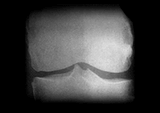

まず問診や触診を行った上で、関節のすき間や変形などの状態を調べるレントゲン(X線)検査が行われます。このとき診断によく使われるのが、変形性ひざ関節症の重症度を示すグレードという指標。グレードは1から4までに分けられており、2以降が変形性ひざ関節症と診断される基準です。グレード2が初期、3が進行期、4が末期と対応しており、進行に伴って関節の隙間が狭くなったり、骨が大きくとがる骨棘(こつきょく)ができたりします。

Kellgren-Lawrence分類(K-L分類)

変形性ひざ関節症の進行期。ひざ関節の隙間がさらに狭くなったり、はっきり確認できるほどの骨棘や骨硬化が生じたりする。